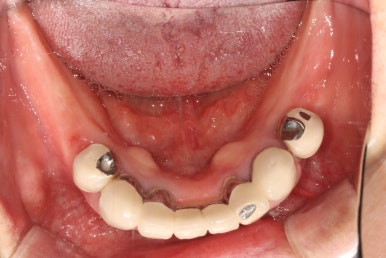

사실 이미 임플란트 치료를 여러개 받아보신 분이었습니다.

위턱 전체 임플란트는 타치과에서 치료가 완료된 상태였고, 비용 문제로 아래 부분틀니만 아직 사용중이신 상태였어요.

아래 틀니를 끼지 않은 상태에서 초진 정면 사진입니다.

기존에 치료받으신 임플란트의 metal 부분이 조금 비추긴 하나, 전체적으로 나쁘지 않습니다.

잘 보시면 아래턱의 맨 끝 치아 두개는 유독 치태가 많이 쌓여있고, 그 앞 치아들로부터 떨어져있는 것을 보실 수 있습니다.

화살표 표시해둔 두 개의 아래턱 작은 어금니는, 아래 부분틀니의 고리가 걸리는 치아입니다.

처음 아래 부분틀니를 제작할 당시에 여러개의 치아를 보철물로 묶어서 제작해드렸어야 하는데, 보시다시피 single crown으로 제작되어있는지라 성인 여성의 저작력을 견디지 못하고 만성치주염으로 흔들거리는 상태가 되었죠... 보면 치과용 파노라마 사진에서 두 치아 주변으로 까맣게 잇몸뼈 소실이 관찰됩니다.

위턱은 임플란트로 어느 정도 치아 자리가 채워져 있는 모습이지만, 아래턱은 어금니가 상당히 많이 없네요.

임플란트로 모두 치료해보기로 하였습니다.